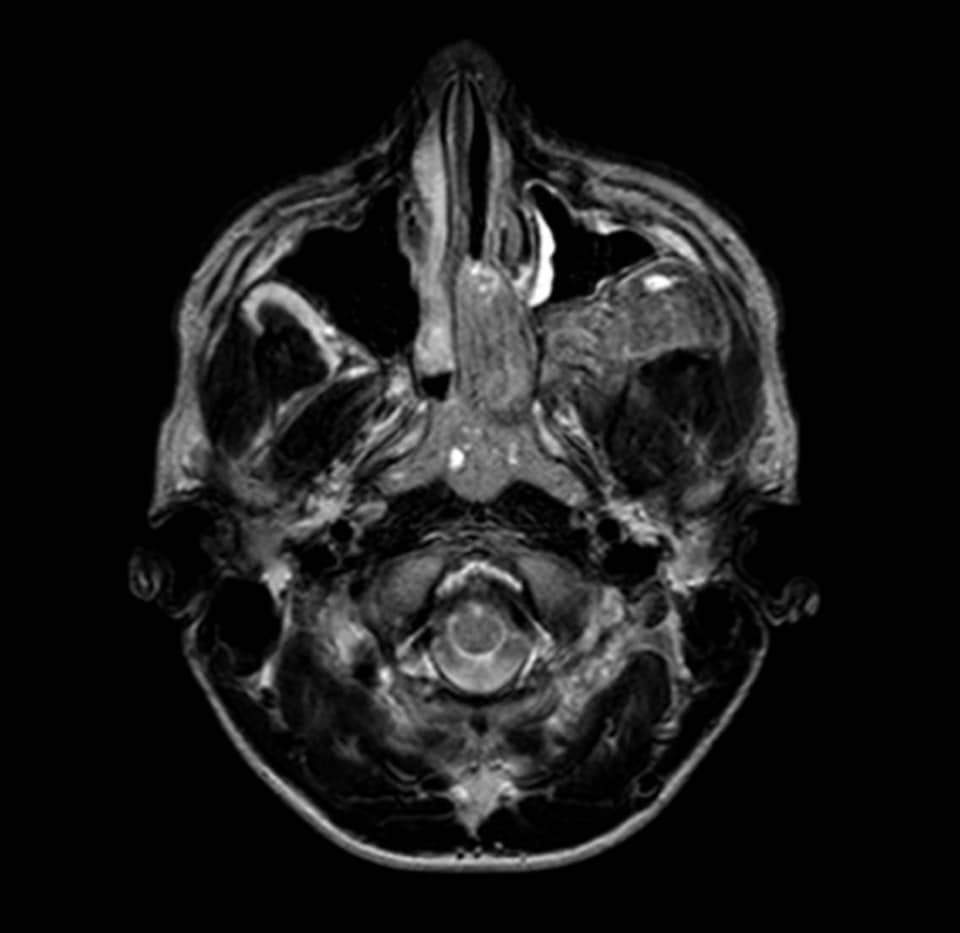

Tumor benigno (no canceroso) formado por vasos sanguíneos y tejido fibroso. Los angiofibromas nasofaríngeos juveniles aparecen en la parte posterior de la nariz y a veces se diseminan a la parte superior de la garganta, los senos paranasales y los huesos que rodean los ojos; en muy pocas ocasiones se diseminan al cerebro. Los signos y síntomas son secreción nasal, hemorragia nasal, dificultad para respirar por la nariz, sordera y tendencia a formar moretones. Los angiofibromas nasofaríngeos juveniles son más frecuentes en hombres jóvenes. Son un tipo de tumor vascular.

Imágenes de resonancia magnética.